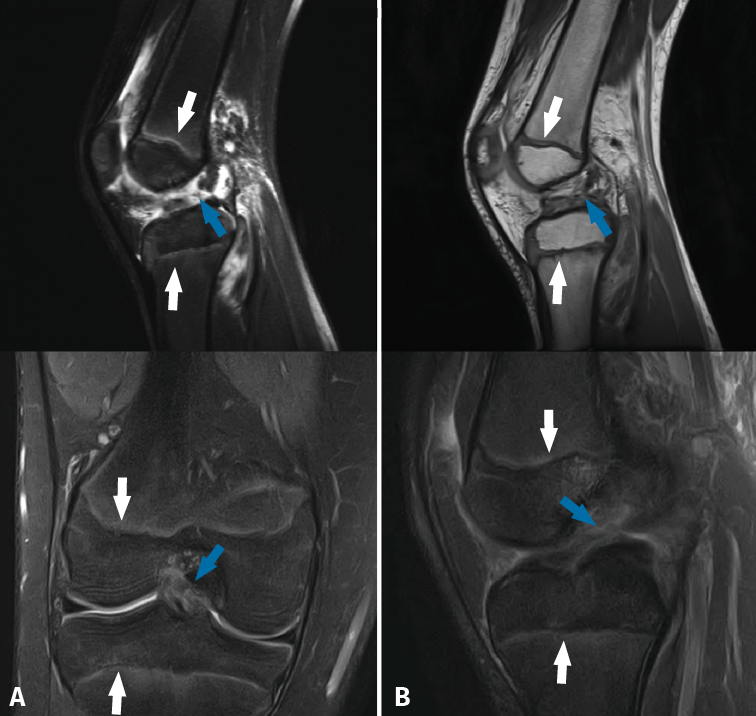

Magnetic resonance imaging shows the physes in great detail in both the distal femur and in the proximal tibia (Figure 3), and is the best technique for evaluating them(30). The presence of the physes can complicate the diagnosis of ligament lesions in immature patients(32).

Figure 3. Magnetic resonance imaging views of the knee in two children with open physes (white arrows), presenting rupture of the anterior cruciate ligament (blue arrow).